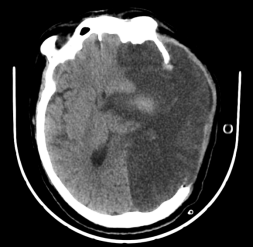

图片

入院时颅脑CT

范大爷入院时呈浅昏迷状,呼之不应,气管切开状态,脑病科何飞主任凭借其精湛的医术和丰富的经验,对范大爷的病情进行了全面细致的评估,组织科室医务人员制定了个性化的中西医结合治疗方案。经过脑病科医务人员精心治疗,范大爷于 2024 年 06 月 24 日神志恢复,偶有嗜睡但可遵嘱活动。